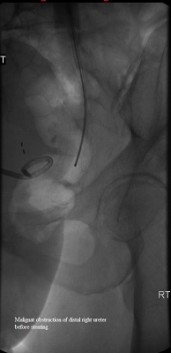

Distal right ureter before dilation and nephroureteral catheterization

Published July 12, 2014 at 171 × 353 in Bilateral insertion of nephroureteral stents after balloon dilation of malignant obstruction of the distal ureters. Ken U. Ekechukwu, MD, MPH, FACP..

Distal right ureter before dilation.